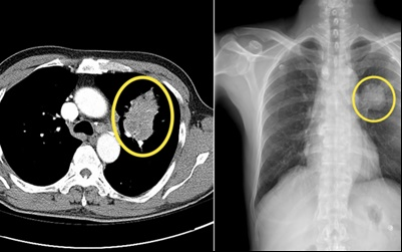

6. 폐암 초기 증상 - 혈담

혈전은 반드시 폐암이 아니어도 나타날 수 있습니다 . 혈담이란 기침 후에 피가 나오 거나 가래에 피가 섞여 있는 것을 혈담 이라고 합니다 . 그러나, 의심스러운 폐암의 초기 증상의 혈담은, 선홍색의 비교적 선명한 피가 나오는 것을 의심해 봐야 합니다 . 이것은 암세포 때문에 폐가 괴사하기 때문 입니다 . 이 경우 폐암 초기보다는 암세포가 확장되었다고 보는 것이 좋습니다 . 폐암 환자의 25% 가 혈담을 했다고 통계가 나온 적이 있습니다 .